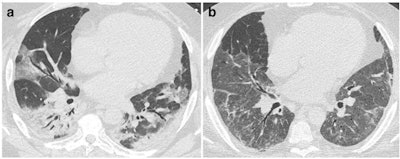

- Post-COVID-19 pneumonia changes are mainly consistent with prior organizing pneumonia and are likely to disappear within 12 months of recovery from the acute infection in the majority of patients.

- Residual ground glass opacification may be associated with persisting bronchial dilatation and distortion and might be termed "fibrotic-like changes" probably consistent with prior organizing pneumonia.